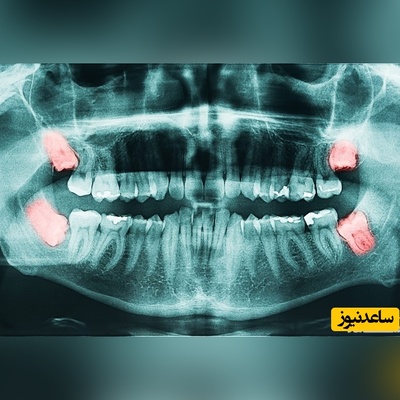

عصب کشی

خدمات بهترین متخصص جراحی لثه چه مواردی را شامل می شود؟

مراقبت های پس از درمان ریشه ی دندان کدامند؟

کشیدن یا عصب کشی دندان شیری ؟ کدام یک بهتر است؟

نکاتی برای جلوگیری از عصب کشی در بارداری

عصب کشی در بارداری امکان پذیر است؟